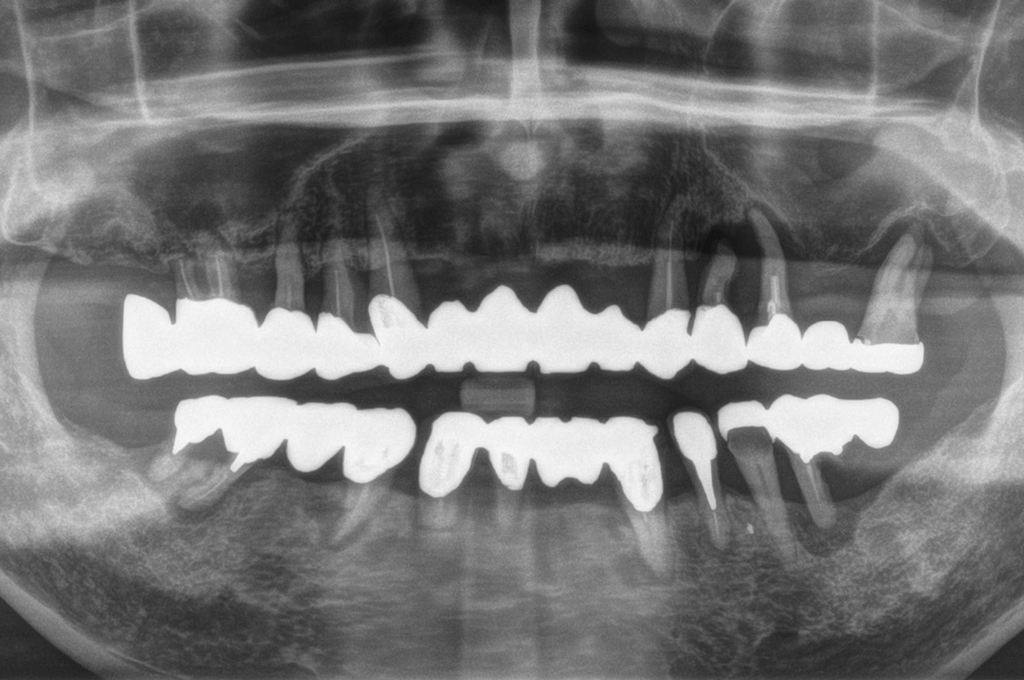

歯周病で噛めなくなってしまった方の上下オールオン4症例

歯周病が進行して支える骨がやせてしまい、すべての歯がグラグラしている状態で受診された患者様です(50代男性)。

術前に歯周病治療をしっかり行ってから、インプラントを埋入しました。オペ当日に仮歯が入り、噛めるようになって喜んでいただきました。

ブリッジ揺れて噛めない、全ての歯が動揺している

上顎・下顎ともにオールオン4